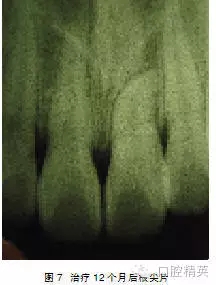

處理:行外科開窗+正畸牽引治療,6個月后破齦萌出,連續(xù)牽引,12個月后到位(圖5~7)。